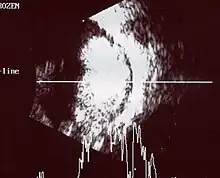

Traditional ultrasound B scan can detect calcifications in the tumour while high-frequency ultrasound B scan is able to provide higher resolution than the traditional ultrasound and determine the proximity of the tumour with front portion of the eye. MRI scan can detect high-risk features such as optic nerve invasion; choroidal invasion, scleral invasion, and intracranial invasion. CT scan is generally avoided because radiation can stimulate the formation of more eye tumours in those with RB1 genetic mutation.[24]

An ocular ultrasound of a large retinoblastoma tumor within the eye of a 3-year-old boy -